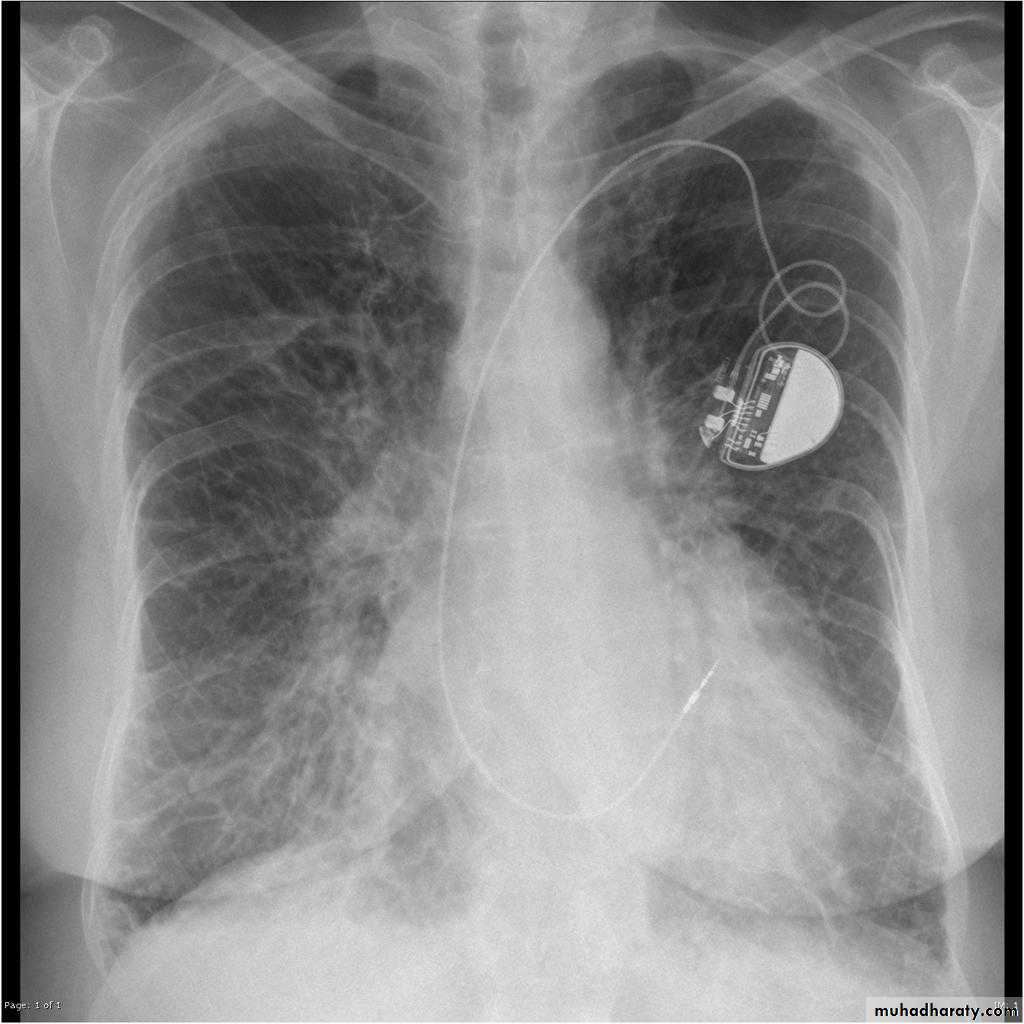

Pulmonary arterial hypertension results from elevation of the resistance in the pulmonary arterial bed, usually at the arteriolar level. It is characterized radiographically by enlargement of the pulmonary trunk and right and left main pulmonary arteries with disproportionately small peripheral vessels This has been referred to as "pruning" of the pulmonary arteries

So the Plain radiograph

elevated cardiac apex due to right ventricular hypertrophy

enlarged right atrium

prominent pulmonary outflow tract

enlarged pulmonary arteries

pruning of peripheral pulmonary vessels